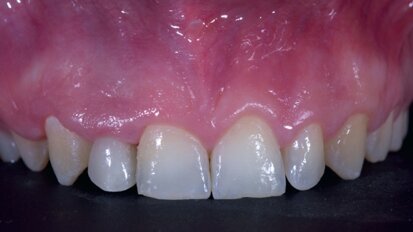

Free webinar: Expert to lecture on implant placement in the aesthetic zone

BERLIN, Germany: Some experts now believe that in order to obtain stable results in the medium and long term, the aesthetic zone should be treated in most ...